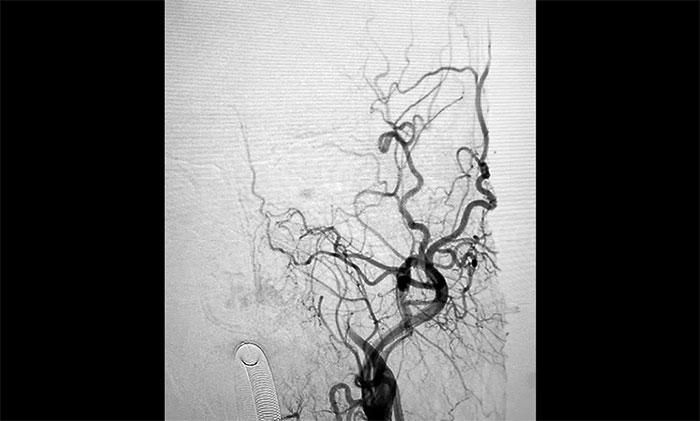

▲術(shù)前DSA影像:左側(cè)頸內(nèi)動(dòng)脈眼動(dòng)脈段以遠(yuǎn)閉塞

▲術(shù)后DSA影像:左側(cè)頸內(nèi)動(dòng)脈血流恢復(fù)

術(shù)中腦血管造影可見:左側(cè)頸內(nèi)動(dòng)脈眼動(dòng)脈段以遠(yuǎn)閉塞……余血管未見明顯異常。張琪博士在劉春、周林華、李喆醫(yī)生協(xié)助下,通過右側(cè)股動(dòng)脈穿刺,將微導(dǎo)管、微導(dǎo)絲送達(dá)左側(cè)大腦中動(dòng)脈M1段,經(jīng)多次抽吸+支架拉栓,順利取出血栓。造影顯示,頸內(nèi)動(dòng)脈眼動(dòng)脈段血流恢復(fù)。

隨后,微導(dǎo)絲超選至左側(cè)大腦中動(dòng)脈M1段遠(yuǎn)端,并以多枚球囊擴(kuò)張殘余重度狹窄處,造影提示狹窄較前明顯改善,遠(yuǎn)端血流改善明顯。最后順利放入支架,造影提示支架貼壁良好,支架內(nèi)血流通暢,遠(yuǎn)端血流良好,手術(shù)順利完成。